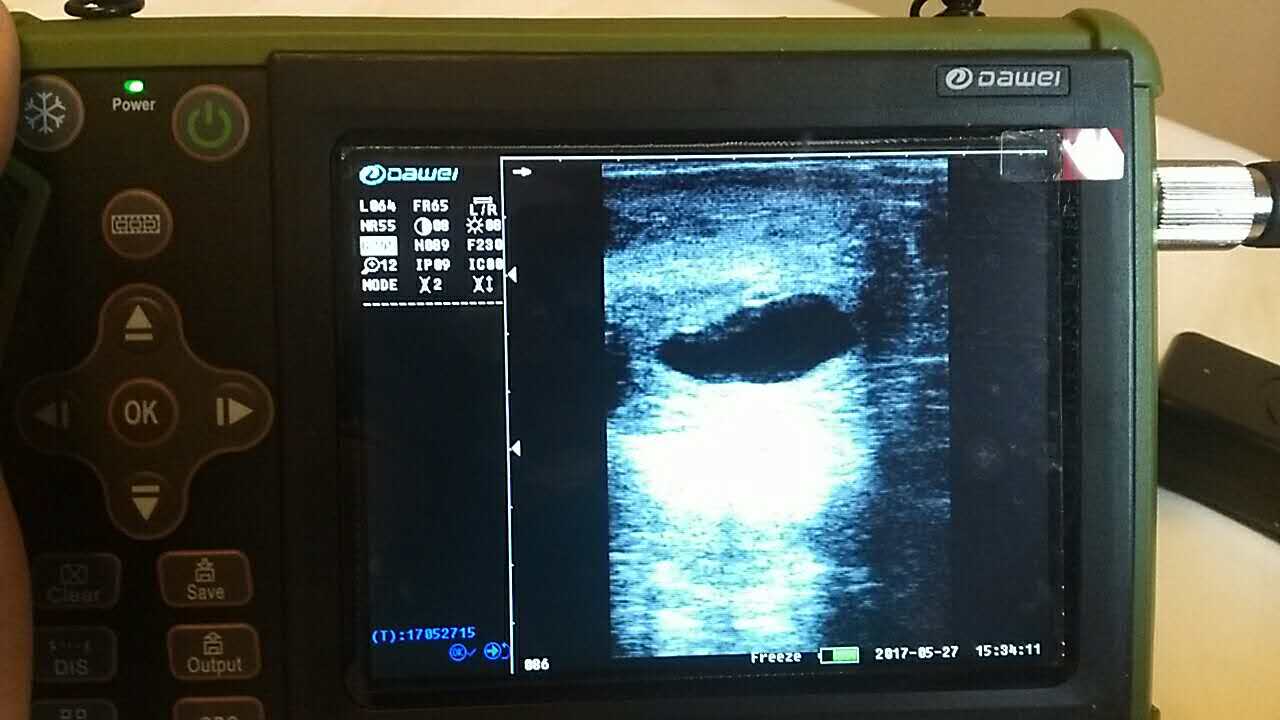

養殖基地140只生產母羊集體接受了B超檢查,利用現代化技術方法,解決生產母羊繁育難題促進畜牧業生產結構的調整。 在檢查中,技術人員拿著B超儀器,給生產母羊做免費受孕普查。用B超檢測母羊受孕情況,用這種方法給母羊做檢測可以準確掌握母羊是否受孕、母羊生產周期。通過B超早期孕檢和生殖系統疾病診斷,可以清晰的觀測到生產的宮腔和胎兒的生產發育情況。除了幫助基地對問題羊做出正確診斷,提出合理的治療方案,淘汰無治療價值的長期空懷羊,還能提高受孕率,降低飼養成本,有效規避了假妊娠造成的經濟損失。

檢測懷孕 估測胎仔數 疾病診斷 胎兒活力鑒定 胎心搏動 適用對象:適用于羊、豬、狗等動物受孕診斷(集成6種常見動物孕周測量數據包) 適用范圍:規模化豬場,人工授精站,飼料/獸藥經銷商及企業,科研教學單位 |